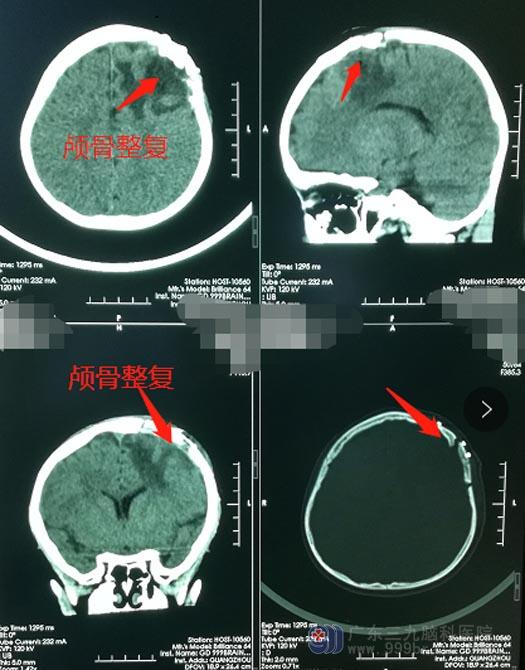

鹏鹏的爸爸妈妈一致同意手术治疗。排除手术禁忌症、完善各项术前准备后,神经外五科鲁明治疗团队在全麻下为患儿施行“左侧额骨生长性颅骨缺损修补术+硬脑膜修补术”,手术顺利。术后鹏鹏的各项生命体征平稳,对答切题,四肢活动良好。